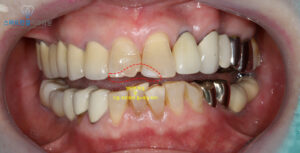

위 환자분은 앞니 파절과

기존 레진 치료 부위의 색상 차이로 인해

보기 싫다고 내원해 주셨는데요.

확인해보니,

오른쪽 위 앞니는 일부가 파절된 상태였으며

왼쪽 위 앞니는 예전에 시행한

레진의 색상이 자연치보다

훨씬 밝아 조화가 맞지 않았어요.

또한 레진과 치아 경계 부위에

미세한 파절이 생겨 틈이 보였는데,

이런 이유들로 인해 웃을 때마다

심미적으로 큰 불편감을 느끼셨답니다.